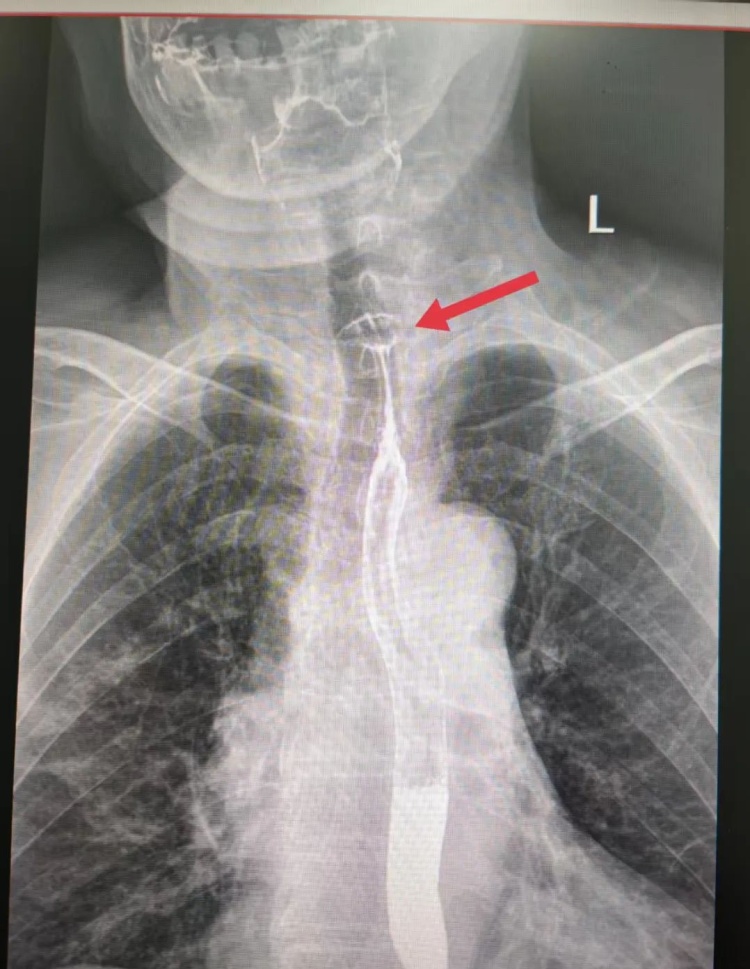

案例一:枣核卡喉 手术脱险

5月28日,陕西榆林75岁的高奶奶食用红枣粽时不慎吞下枣核,顿感咽喉不适、吞咽梗阻,紧急前往医院就诊。检查发现食管上段有异物,高奶奶被收治入院,经手术顺利脱险。

图源:榆林市中医医院